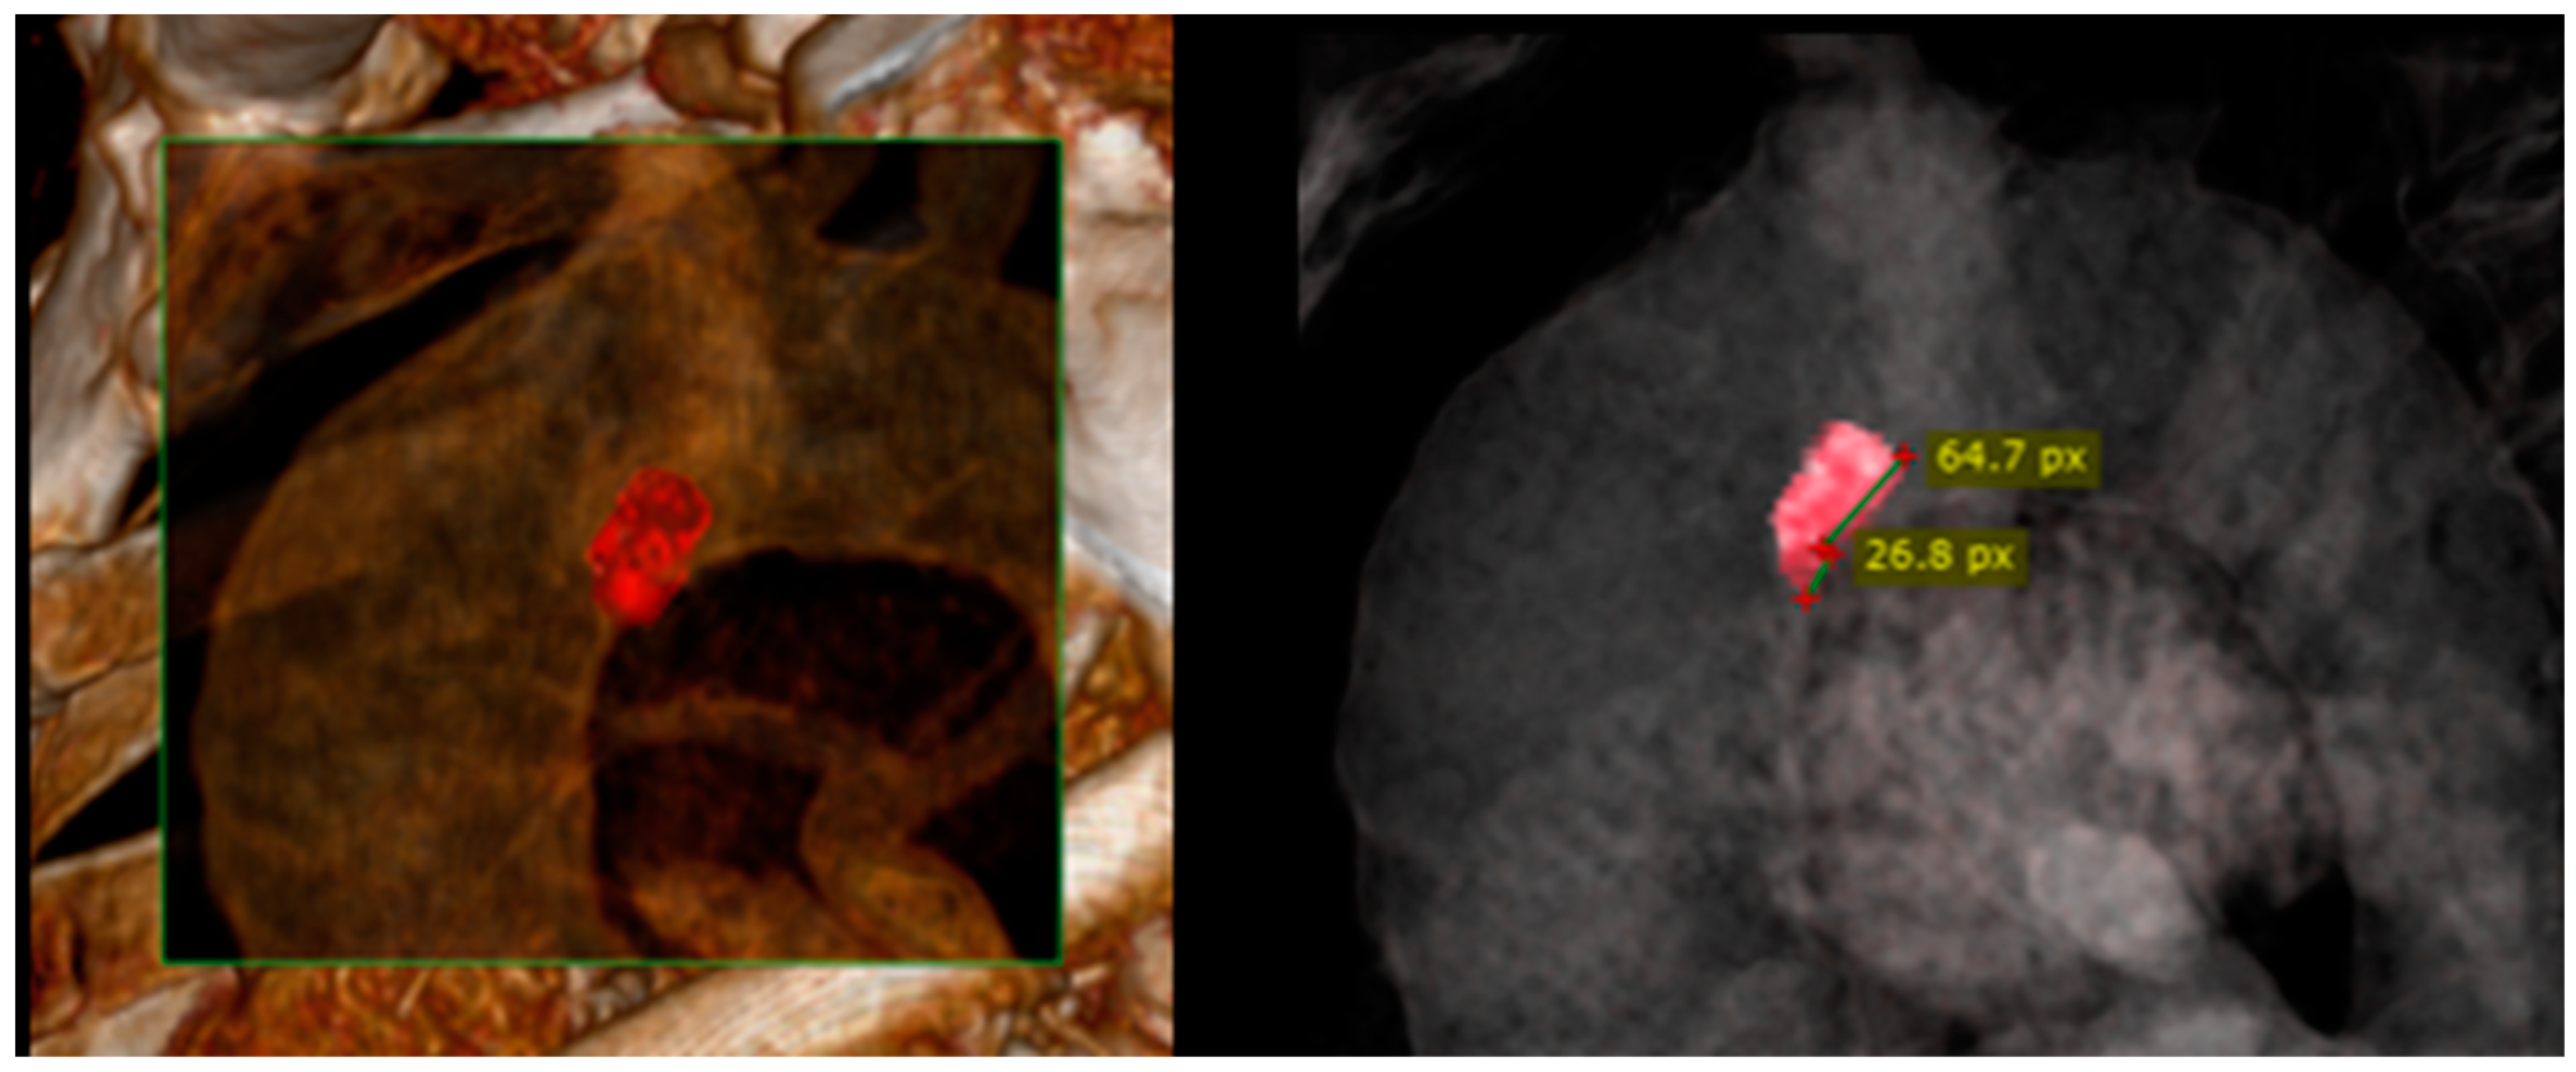

2. Case Presentation